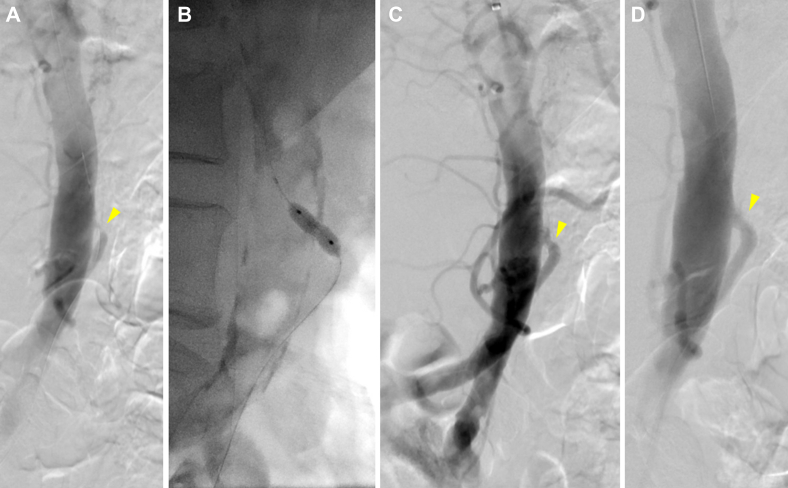

Fig 2.

A, Preoperative flush aortogram of patient 2 showing occlusion of known celiomesenteric trunk with severe proximal inferior mesenteric artery (IMA) stenosis (arrowhead). B, Balloon angioplasty. C, Angiogram showing residual waist and modest improvement. D, Completion angiogram after stenting showing improved IMA flow.

Patient 2

An 83-year-old female patient had presented with a 5-year history of postprandial abdominal pain and a 40-lb weight loss. She underwent elective mesenteric angiography via a left brachial approach, which demonstrated a chronically occluded common celiomesenteric trunk and high-grade focal ostial IMA stenosis. The celiomesenteric trunk occlusion could not be crossed; thus, the IMA was selectively catheterized and stented with a bare metal stent. After stenting, the IMA was noted on flush aortography to briskly fill a prominent meandering mesenteric artery, which filled the celiomesenteric trunk in a retrograde fashion (Fig 2). The patient received a loading dose of clopidogrel and was discharged on POD 2 with a prescription for dual antiplatelet therapy for 6 months. A patent IMA was noted through 1 year of follow-up.